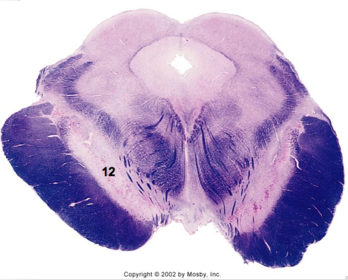

| Medullary pyramids | |

| Hypoglossal nucleus | |

| Hypoglossal nerve | |

| Dorsal motor nucleus of X | |

| Nucleus ambiguus | |

| Solitary tract | |

| Solitary nucleus | |

| ALS | |

| Medial lemniscus | |

| Medial longitudinal fasciculus | |

| Anterior spinocerebellar tract | |

| CN IX | |

| Inferior cerebellar peduncle | |

| Inferior olivary complex | |